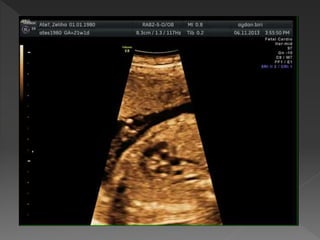

 18-22 hf

 Teknik özellikler